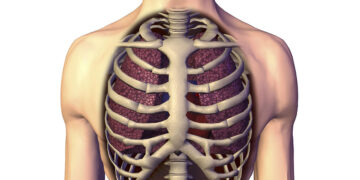

Read moreঅধ্যাপক ডা. ইকবাল হাসান মাহমুদ বুকের মাংসের নিচে হাড় দিয়ে নির্মিত একটি খাঁচা রয়েছে। এই খাঁচার হাড়গুলোর মধ্যে বিভিন্ন ধরনের...